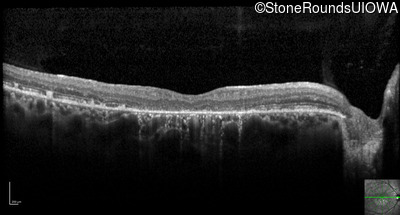

Optical Coherence Tomography - Right - 20/200

Exemplar / OCT Stack